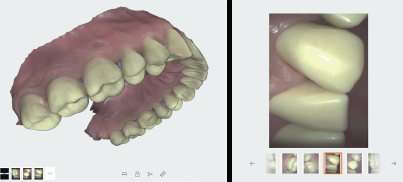

Live View Screenshot

The Live View Screenshot tool enables you to take screenshots during the scanning process, to be included in the Case Review and final Export, allowing you to pinpoint problem areas and monitor treatment progress. It also provides valuable information to technicians on tooth texture, margin definitions, etc..